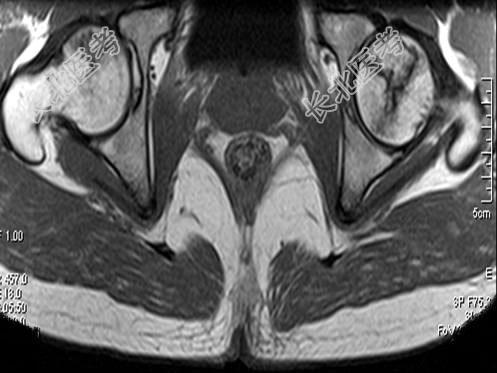

- 单项选择题男,24岁, 曾有外伤史,两侧髋部疼痛不适数月, 结合所提供的图像,最可能的诊断是 ( )

A、股骨头无菌性坏死

B、髋关节退行性变

C、未见异常

D、化脓性骨关节炎

E、类风湿关节炎两侧